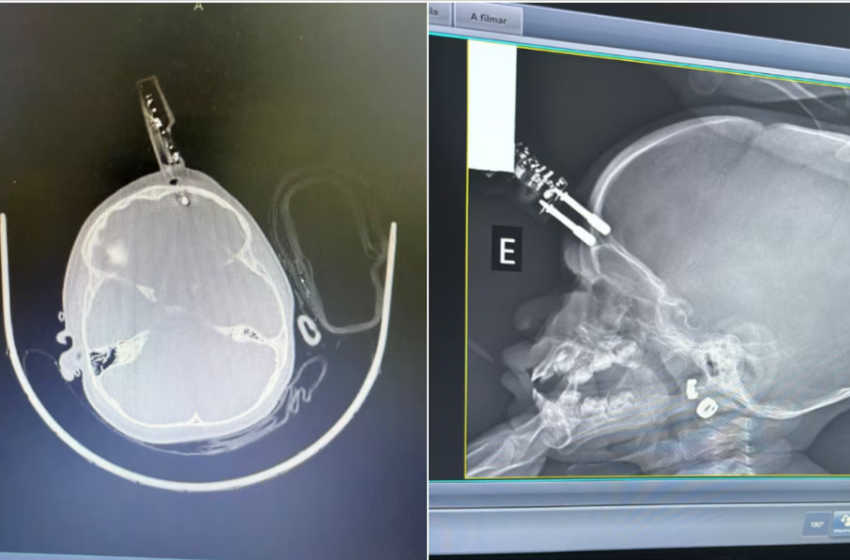

Uma menina de 1 ano e 4 meses precisou passar por cirurgia após sofrer uma perfuração no crânio provocada por um pino de carregador de celular, em Divinópolis, a 117 quilômetros de Belo Horizonte. O objeto chegou a atingir o cérebro da criança, que caiu da cama dentro de casa.

O neurocirurgião Bruno Castro, responsável pelo caso, explicou que a mãe ouviu o choro da filha no quarto e a encontrou caída no chão, com sangramento e um dos pinos do carregador atravessando o crânio na região frontal. Segundo o médico, a tomografia indicou que o pino havia atingido a ponta do lobo frontal, causando lesão cerebral. Ele também destacou que, em crianças dessa idade, o osso do crânio é mais fino, o que facilita perfurações em situações de queda.

Diante do diagnóstico, a menina foi levada ao bloco cirúrgico para retirada do objeto. O procedimento, conforme relatado pelo neurocirurgião, foi rápido e ocorreu sem intercorrências, com controle de um pequeno sangramento e correção da falha óssea.